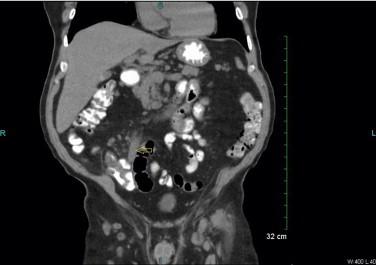

A 75 year old male with a history of left cervical lymphadenopathy biopsied to be mantle cell lymphoma presented with right lower abdomen pain for 3 days. An outpatient CT scan revealed acute appendicitis. Laparoscopic appendectomy was performed without any complication. The histologic examination showed mantle cell lymphoma occluding the lumen of appendix.

一名75岁男性,有左侧颈部淋巴结病活检确诊为套细胞淋巴瘤病史,出现右下腹疼痛3天。门诊CT扫描显示急性阑尾炎。行腹腔镜阑尾切除术,无任何并发症。组织学检查显示套细胞淋巴瘤阻塞阑尾腔。